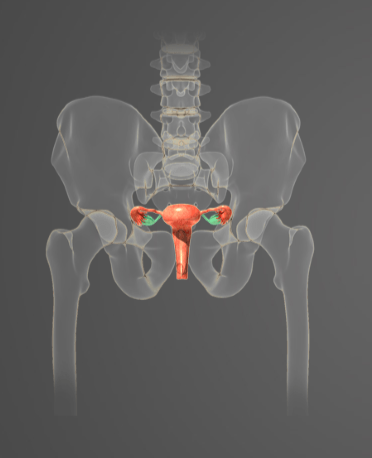

-

Question of

Určete:

-

játra

-

slinné žlázy

-

žaludek

-